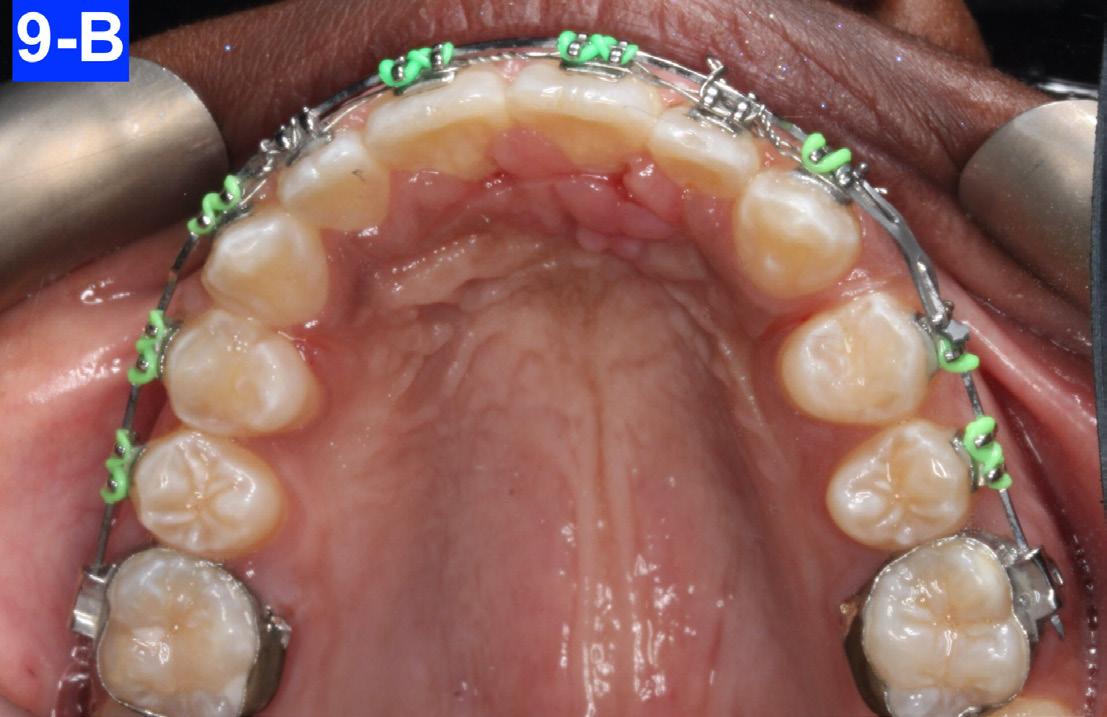

After eight months of treatment, the maxillary habit breaker was removed. We added box elastics (5/16” x 6.5 oz) that were stretched around the mandibular cuspids and maxillary laterals, to accelerate the closing of the anterior open bite. The patient was already very happy with the progress and the amelioration of her posed smile (Figure 9-A, B, C, D).

Fig. 9-B: Maxilla, progress, occlusal view